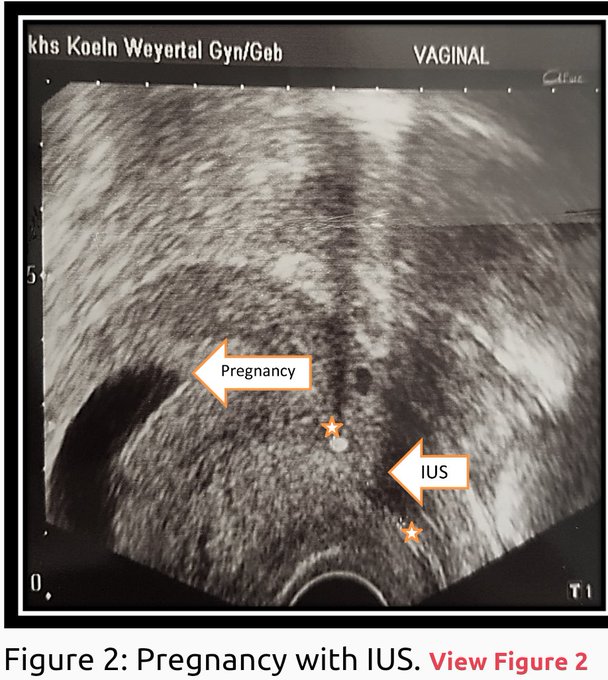

Despite being considered the best contraception, pregnancy can still occur with an IUD. The failure rate is lower than other abortifacients. Usually, women abort the child or if they decide not to kill their child, premature birth, infections, birth defects etc are likely.